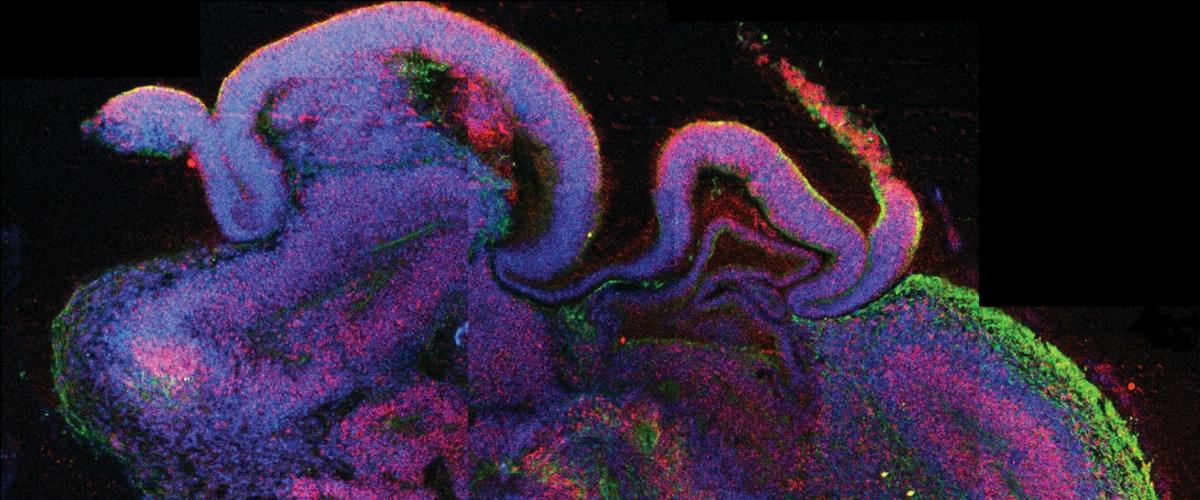

Одним из важнейших достижений современных биотехнологий считается создание мозговых органоидов — упрощенных моделей человеческого мозга размером с горошину. Эти структуры могут использоваться для изучения целого ряда заболеваний, затрагивающих мозг, от вируса Зика до болезней Альцгеймера и Паркинсона, а также тестирования лекарств.

Хотя некоторые органоиды уже демонстрируют такую же электрическую активность, как мозг недоношенных младенцев, ученые уверены, что эти структуры ничего не чувствуют и не обладают сознанием. Это позволяет проводить на них эксперименты без оглядки на этические нормы.